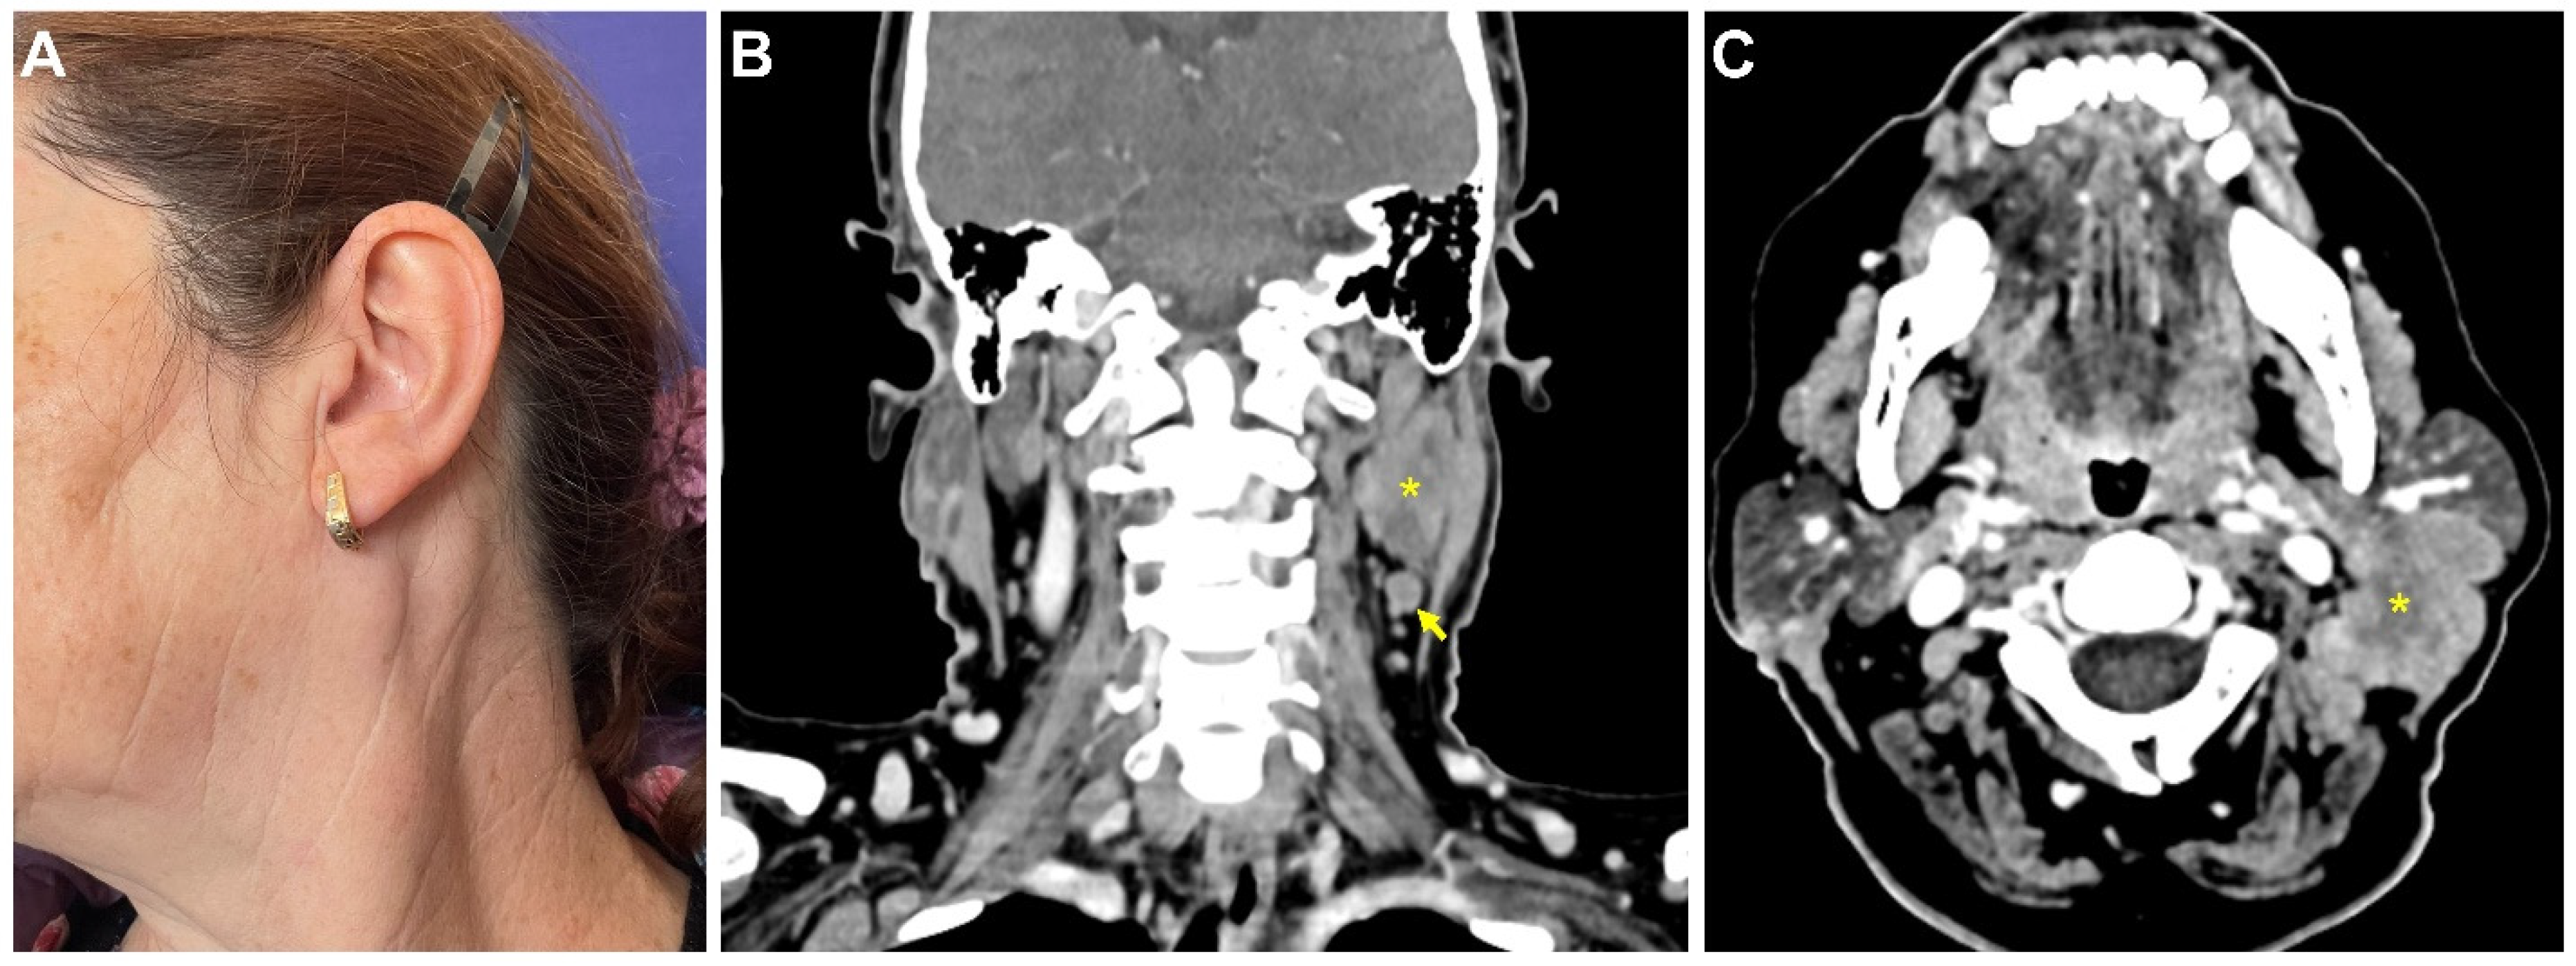

2. Case Report